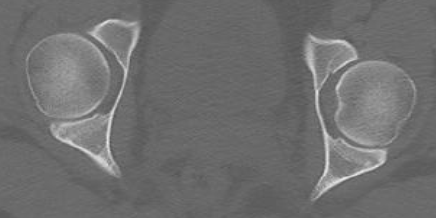

C

Condyles (Arche romaine)